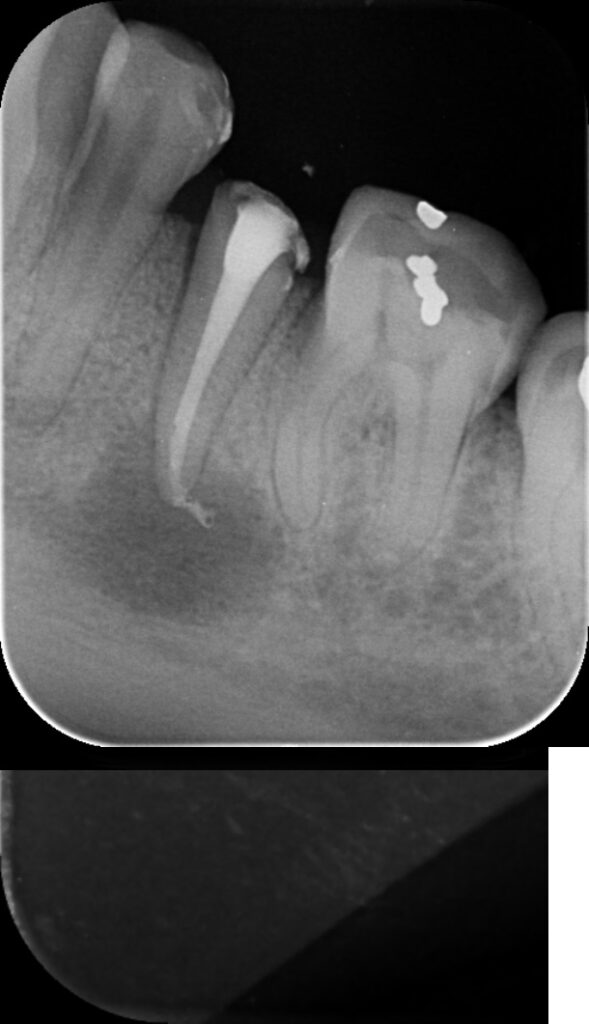

Situation initiale, dent couronnée avec un ÉNORME kyste apical

Apres démontage de la couronne, on débouche la racine…

Apres nombre de désinfections, on rebouche le canal, à la bonne longueur

Mise sous provisoire de la dent, le temps d’être certain qu’on a réussi à soigner l’infection

1 an plus tard, le kyste ne se voit presque plus! Une nouvelle couronne a été installée sur la racine